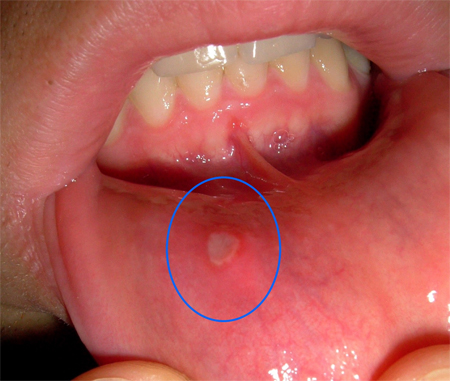

Ağzınızda Çıkan Bezelere Dikkat!

Ağız içinde çıkan küçük bezeler, ağızda ve boÄŸazda tekrarlayan kanamalar, çiÄŸneme ve yutma güçlüÄŸü gibi belirtilere sahipseniz hemen bir diÅŸ hekimine görünmelisiniz. Çünkü bu belirtiler ağız kanseri belirtileri olabilir.

Ağız kanserine dikkat

Ağız ve çene kanserlerinde ağız içinde yanma, aÄŸrı, kitle oluÅŸumu, renk deÄŸiÅŸikliÄŸi ile dudaklarda uyuÅŸukluk, ağızda kötü koku- akıntılar ve uzun sureli iyileÅŸmeyen ülserasyonlar gözlenebilir.